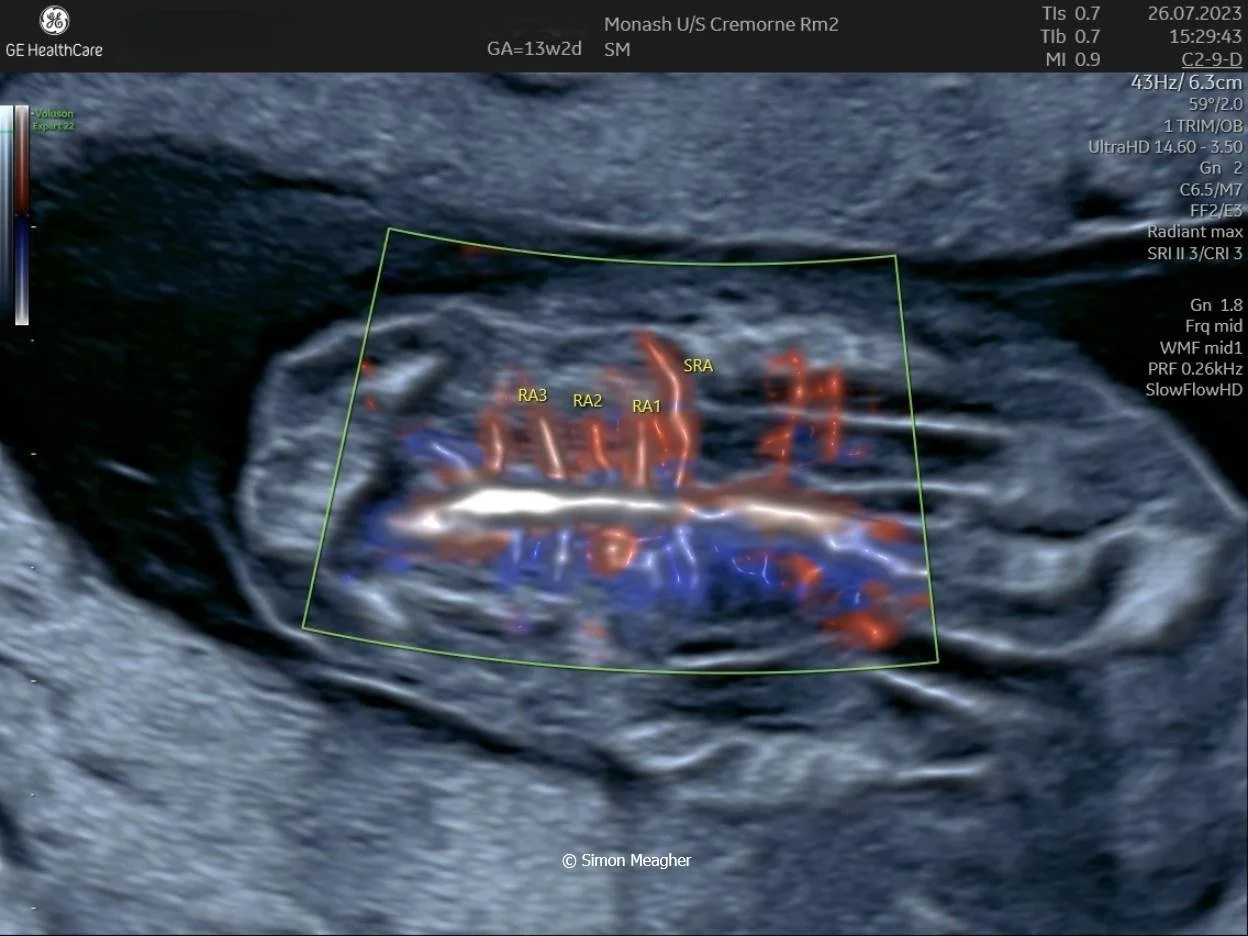

Join Professor Simon Meagher and leading experts for an intensive masterclass designed to transform your clinical practice.

This high-impact, one-day event delivers live scanning demonstrations, real-world case studies, and cutting-edge techniques across all trimesters.